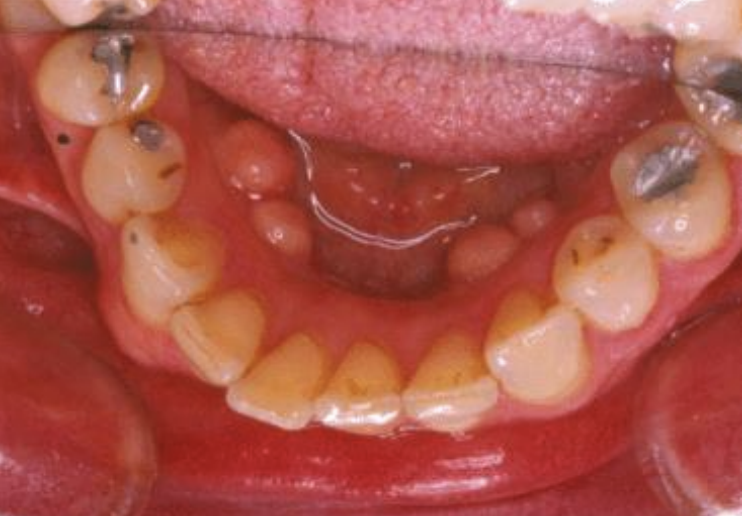

What abnormality is seen in this photo?

A

Mandibular tori